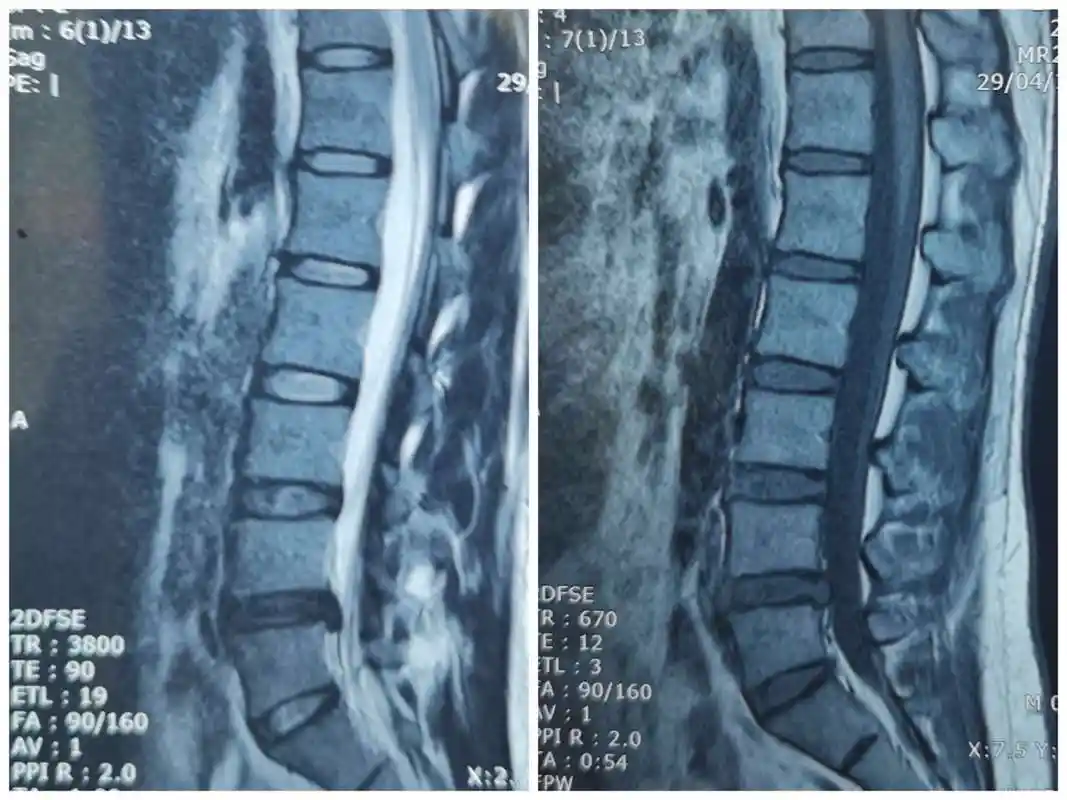

病例分析 | 腰椎间盘突出症综合治疗